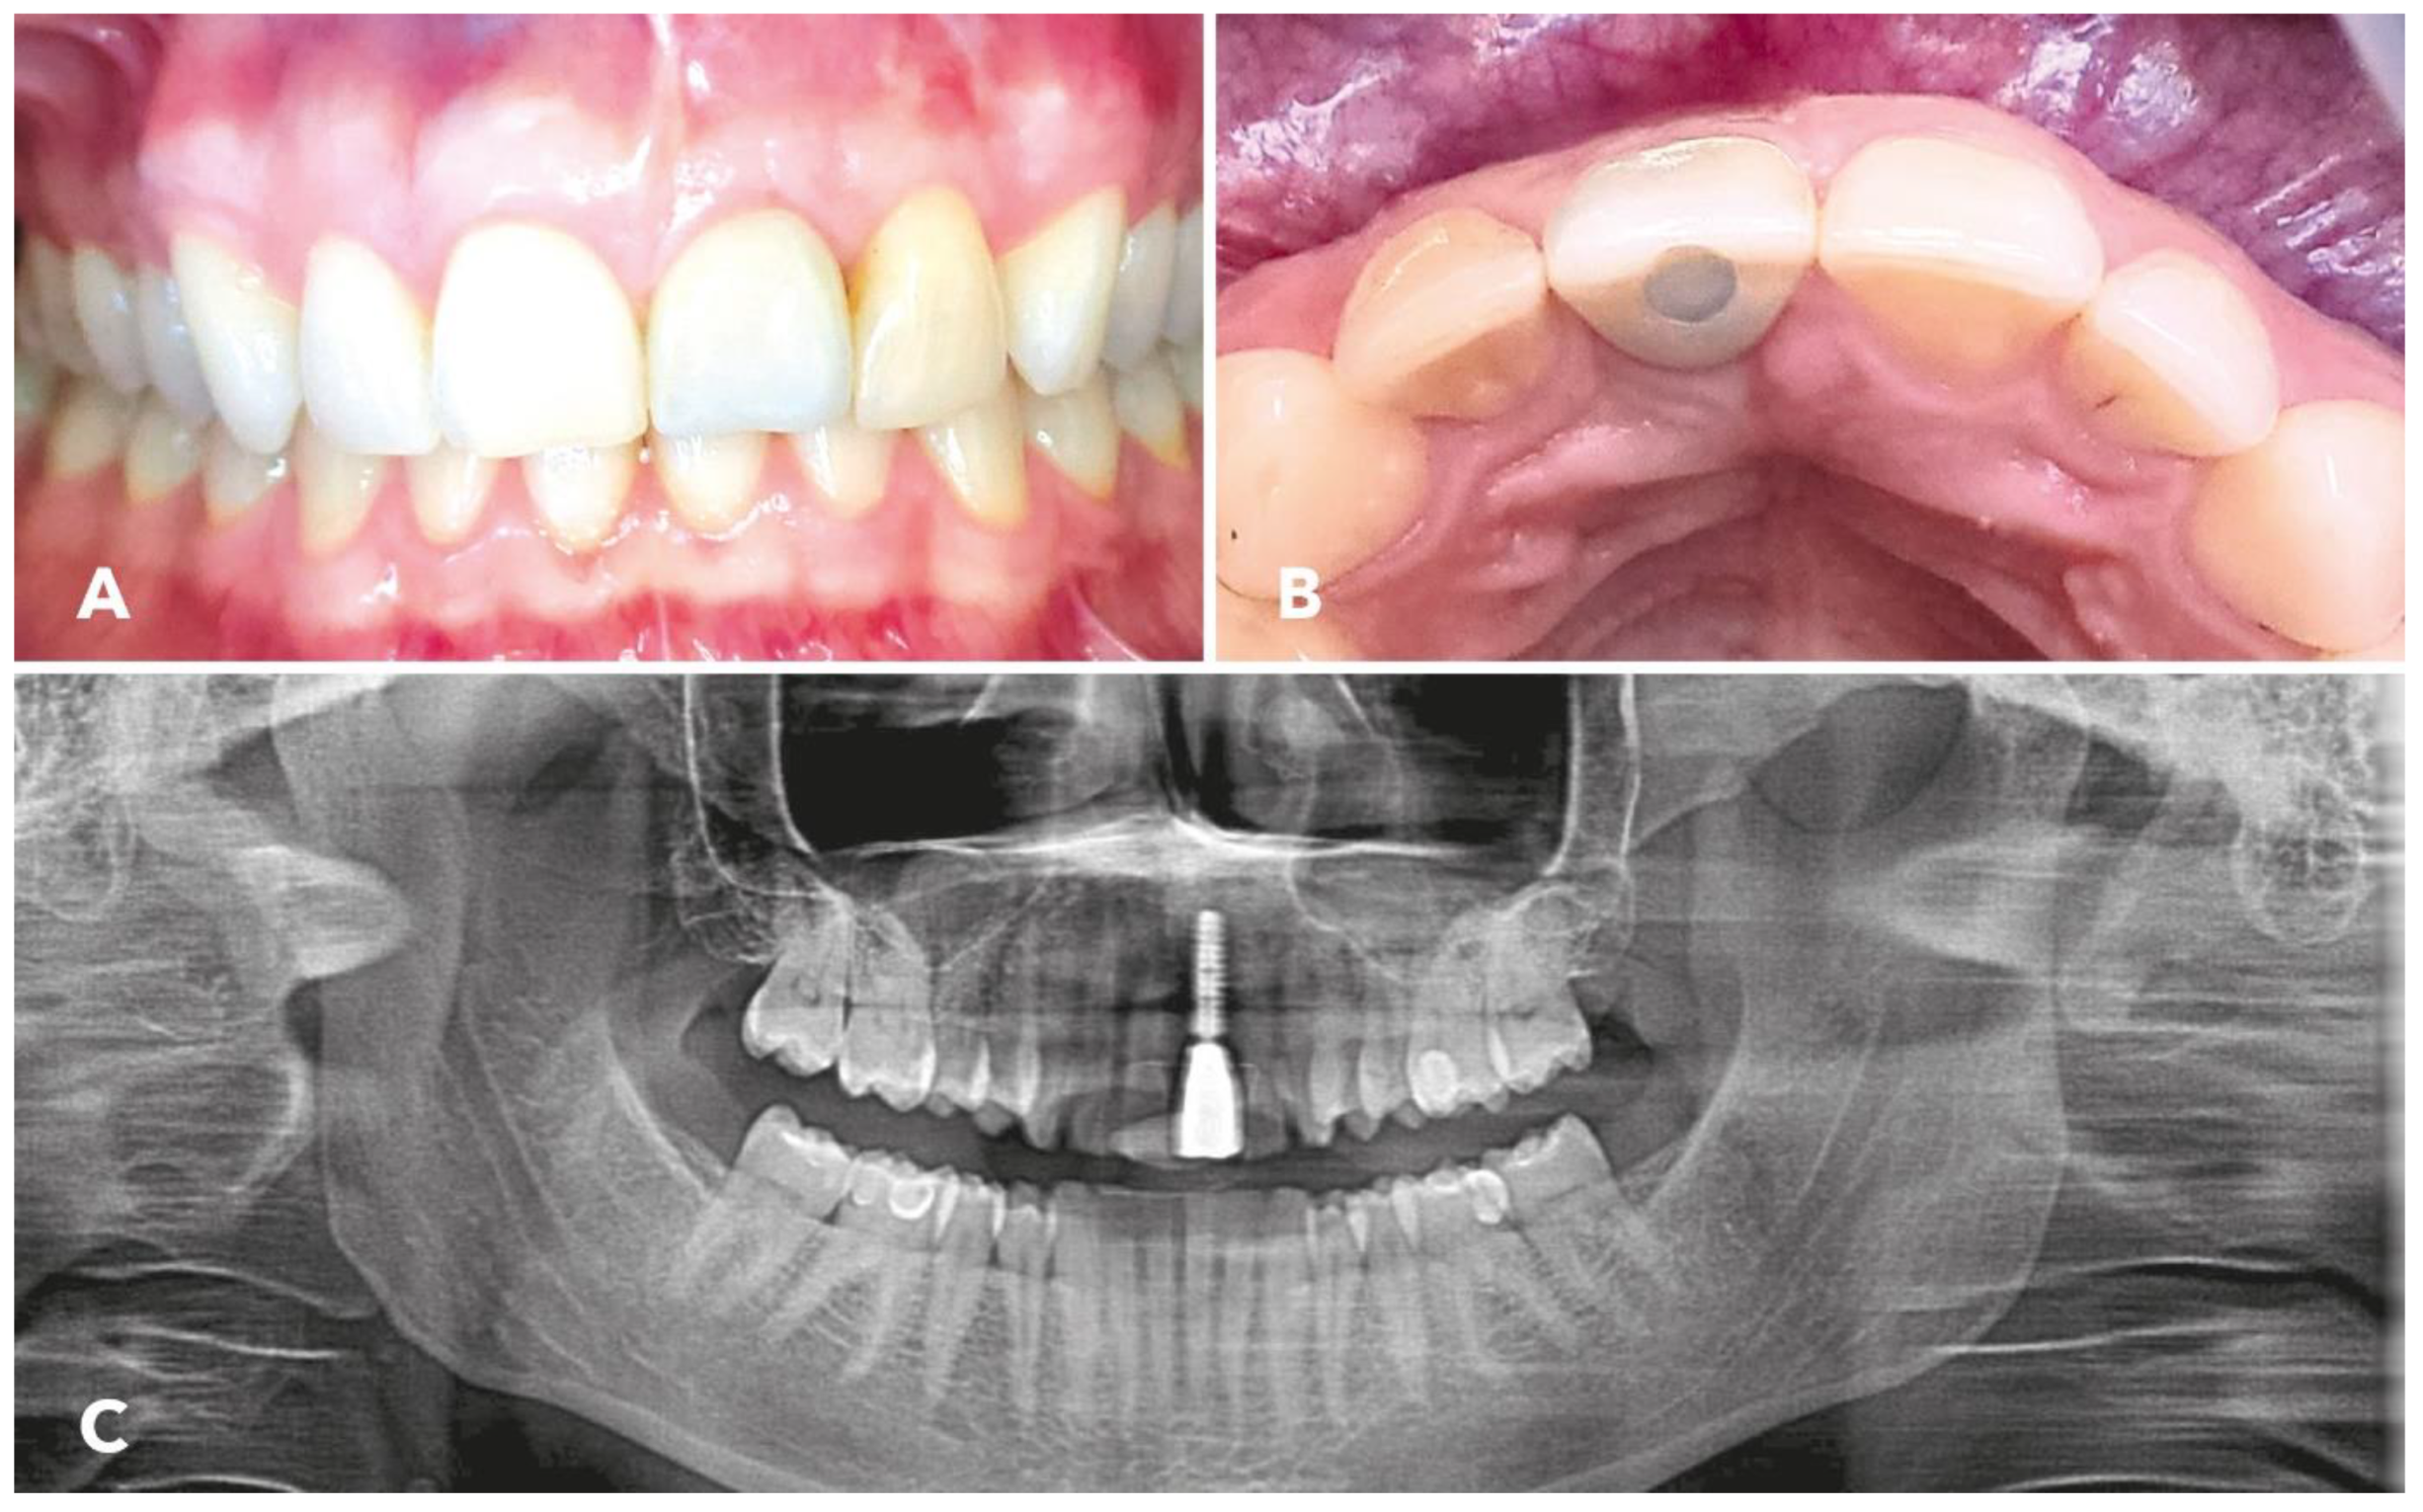

3. Results

4. Discussion